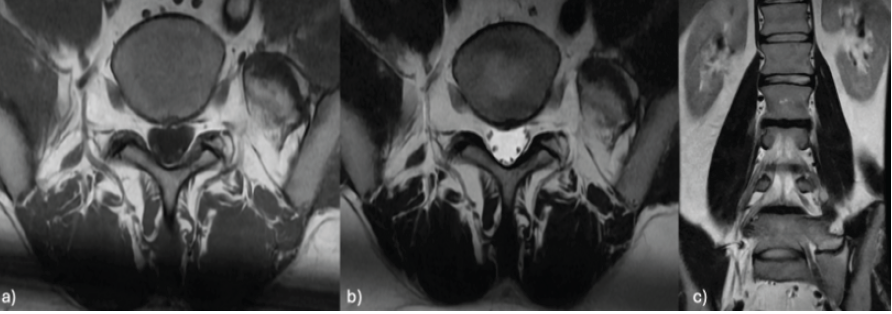

A 33-year-old male presents with long-standing left low back pain with predominantly mechanical characteristics. Pain presents in the morning and quickly improves when the patient is sitting or standing. No radicular pain, paresthesia, or neurologic deficits are present. Upon physical examination, localized left lumbar pain was noted, with no signs of radicular involvement affecting the lower extremities. Imaging studies revealed lumbosacral articulation Castellvi type IIa, with radiological signs of pseudoarthrosis. MRI and X-ray confirmed the presence of LTV with partial fusion between the transverse process and the sacrum. MRI also revealed subchondral bone edema in the contact area between the L5 transverse process and the sacrum, which suggests active mechanical overload (Fig. 1).

Figure 1: Lumbar magnetic resonance imaging in axial T1 (a) and T2 (b) sequences and coronal T2 (c) sequences showing subchondral edema at the contact area between the left L5 mega-transverse process and the sacrum.